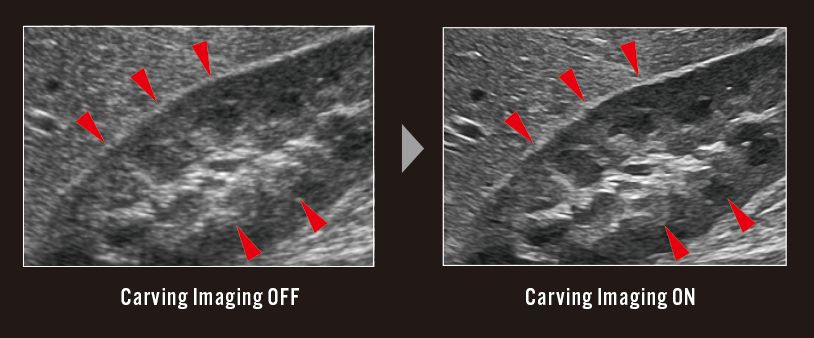

DeepInsight, which is an advanced noise reduction technology, eFocusing PLUS and Carving Imaging. The combination of these technologies enhances the signal from the tissues and delivers higher image quality with far less examiner dependency.

Tissue structures such as vessel wall can be delineated clearly keeping the texture and the expression of surrounding tissue. The evolved edge emphasis processing technology can extract the structures effectively.

Definite imaging technologies succeeded from premium class models delivers all users high image quality that allows the detection of even fine changes.